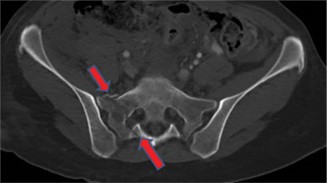

التشخيص الدقيق لخراج العمود الفقري: تقنيات الأستاذ الدكتور محمد هطيف المتطورة

التشخيص المبكر والدقيق لخراج العمود الفقري هو حجر الزاوية في العلاج الناجح ومنع المضاعفات المدمرة. يتطلب ذلك نهجًا شاملاً يجمع بين الفحص السريري الدقيق، الفحوصات المخبرية، وأحدث تقنيات التصوير المتقدمة. الأستاذ الدكتور محمد هطيف، بخبرته الواسعة واستخدامه لأحدث الأجهزة التشخيصية، يضمن الحصول على أدق النتائج لتحديد خطة العلاج المثلى.

3. التصوير المتقدم: الأدوات الذهبية للتشخيص

- التصوير بالرنين المغناطيسي (Magnetic Resonance Imaging - MRI):

- الأداة الذهبية: يعتبر التصوير بالرنين المغناطيسي هو الفحص التشخيصي الأكثر دقة وحساسية لتحديد خراج العمود الفقري.

- المعلومات التي يقدمها: يوضح MRI بوضوح موقع الخراج، حجمه، مدى امتداده، علاقته بالحبل الشوكي والأعصاب، ودرجة الضغط عليها. يمكنه أيضًا الكشف عن أي التهاب عظم ونقي مصاحب في الفقرات.

- الصبغة (Contrast Enhancement): غالبًا ما يتم استخدام صبغة الغادولينيوم لتحسين رؤية الخراج وتمييزه عن